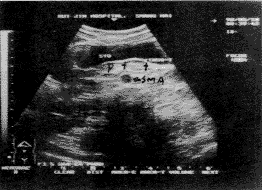

32例胰岛细胞瘤中功能性胰岛细胞瘤29例,占90.62%,非功能性胰岛细胞瘤3例,占9.38%;28例胰岛素瘤中良性27例,占96.43%,恶性1例,占3.57%;小于2cm肿瘤22例23枚(图1、2),占82.14%;肿瘤在胰头、胰体、胰尾的分布大致相等。

STO:胃,P:胰腺,SMA:肠系膜上动脉,双“+”之间即胰岛细胞瘤

图1 胰体胰岛细胞瘤